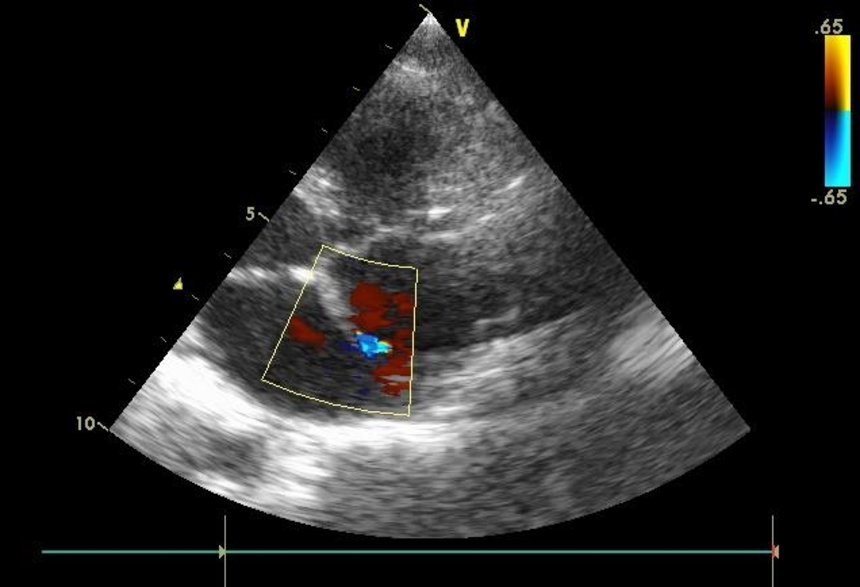

- Эхокардиография – ультразвуковое исследование, позволяющее получить данные о патологиях сердца и его внутренней гемодинамике.

- УЗИ сердца с допплером – методика, позволяющая врачу визуально оценить процессы кровотока, состояние сердечных клапанов и коронарных сосудов с помощью прикрепления специальных датчиков в области грудной клетки пациента.

Врожденные пороки сердца диагностирует неонатолог (порок сердца у новорожденных), семейный врач, педиатр (порок сердца у детей), терапевт (врожденный порок сердца у взрослых), детский кардиолог, кардиолог, специалист по ультразвуковой диагностике, эндоваскулярный хирург, кардиохирург. Самый доступный, безопасный и при этом очень информативный инструментальный метод диагностики – ЭхоКГ с допплерографией. Для диагностики сложных врожденных пороков сердца применяют рентген контрастное исследование (вентрикулографию, ангиографию), КТ и МРТ, в том числе с контрастированием.

Врожденный порок сердца диагностируют не только после рождения, но и внутриутробно с помощью ЭхоКГ с допплерографией

Основным способом выявления патологии у ребенка является УЗИ сердца. Альтернативное название манипуляции – ЭХО-кардиография. Данная процедура абсолютно безболезненна и безопасна, поэтому является методикой выбора при диагностике многих врожденных патологий сердца. Для того чтобы увеличить информативность исследования, необходимо использовать современные аппараты УЗИ, а прием должны вести опытные специалисты, которые способны заметить даже небольшие нарушения гемодинамики. Такой подход позволяет обеспечить достоверную диагностику патологий даже у самых маленьких пациентов.